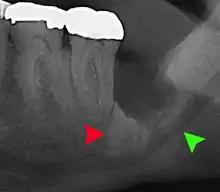

| 3D CT of an impacted wisdom tooth adjacent the inferior alveolar nerve prior to removal of wisdom tooth | |

Coronectomy is a procedure where the crown of the impacted wisdom tooth is removed, but the roots are intentionally left in place. It is indicated when there is no disease of the dental pulp or infection around the crown of the tooth, and there is a high risk of inferior alveolar nerve injury.[32]

Coronectomy, while lessening the immediate risk to the inferior alveolar nerve function has its own complication rates and can result in repeated surgeries. Between 2.3% and 38.3% of roots loosen during the procedure and need to be removed and up to 4.9% of cases require reoperation due to persistent pain, root exposure or persistent infection. The roots have also been reported to migrate in 13.2% to 85.9% of cases.[32]